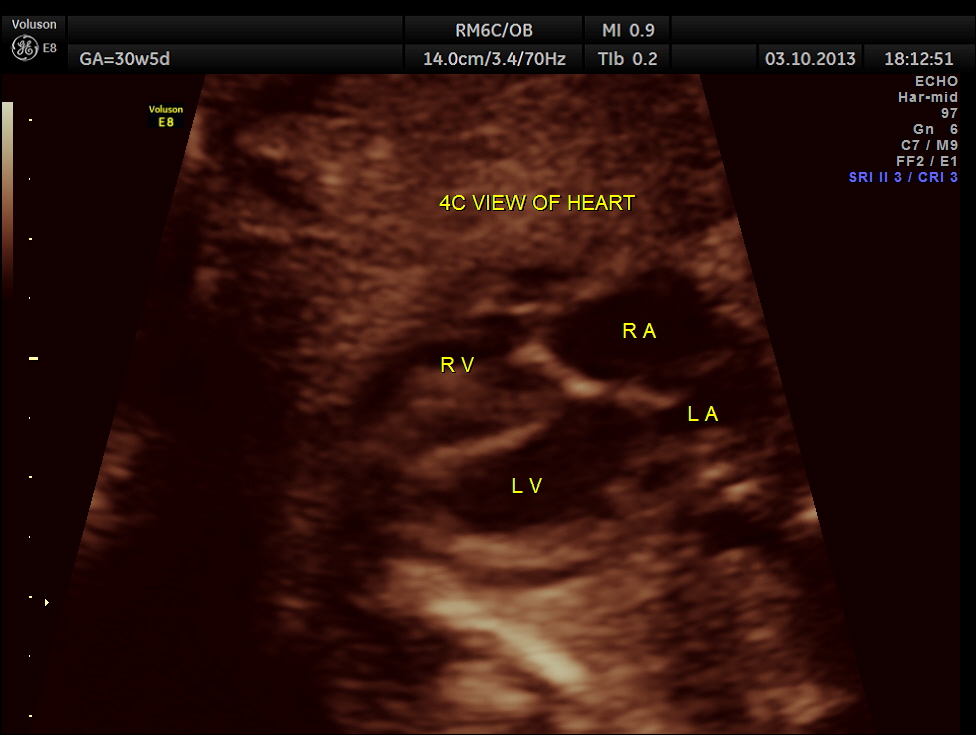

The following pictures belong to two scans done at 31 weeks of gestation.

The rest of the scan appeared normal.